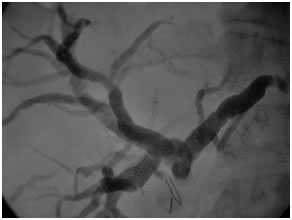

Vascular narrowing of R PV in type 3b